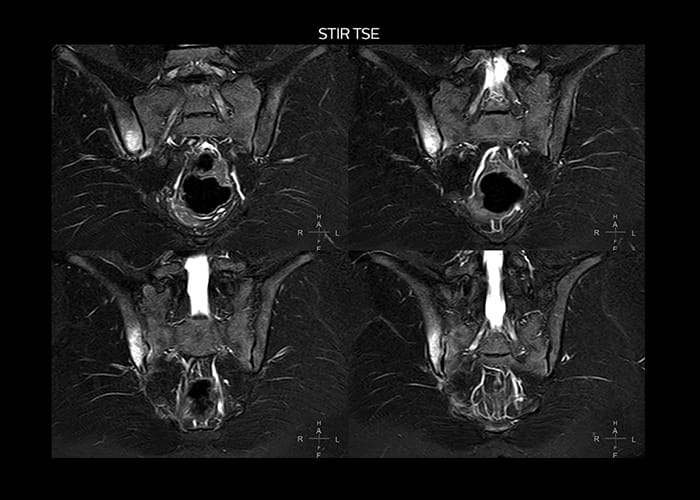

“On average, we scan about 80 patients per day, but on some days we scan well over 100 patients. The scanner is in use 7 days per week, operated 20 hours per day on week days and 8 hours per day in the weekend,” Mr. Tuna says. “To avoid coil changes we plan examinations of similar anatomies back to back, such as head and spine. Multiva helps us here a lot because coils don’t need to be changed frequently. Moreover, thanks to parallel imaging technology and 16-channel HeadSpineTorso and 8-channel MSK coils we are able to achieve excellent image quality. In this way Multiva helped us to increase both image quality and productivity.” “Neurological cases, such as brain and spine imaging, represent the largest share in our MR scanning, followed by musculoskeletal cases. In general, we use simple and basic imaging protocols. But occasionally, we use advanced techniques for problematic cases if necessary.

“Since we have Multiva, we have improved our workflow, because it has been so easy for our operators to learn and use Multiva. Our operators notice that the coils are lightweight and coils don’t need to be changed frequently. The user interface is easy to use. Features like this help us to scan a high number of patients. For instance, the musculoskeletal coils can be used interchangeably, and due to the user-friendly interface, the number of mistakes such as, for example, correct coil element selection has decreased significantly, because the system does it automatically by itself.” “Most important, Multiva satisfies our clinical imaging needs very well,” says Mr. Tuna. “Many features of Multiva have become similar to the Ingenia system. Even in more complex imaging such as abdominal and cardiac, the image quality and performance of Multiva is better than we expected. General surgeons and physicians from our hospital’s internal medicine department prefer to refer to us because of this.”

“Overall, Multiva provides what we need in term of patient needs and even potential needs,” says Mr. Tuna. “It allows us to scan a high patient volume and image a large variety of anatomies and conditions.” “Our goal is to achieve uncompromising quality based on universal standards, while solving clinically complex cases. Our Multiva scanner allows high productivity with fast imaging time, and allows us to make confident diagnoses in a broad range of cases.” “It’s an excellent multi-purpose scanner that satisfies all our MR imaging requirements in the hospital,” he concludes.